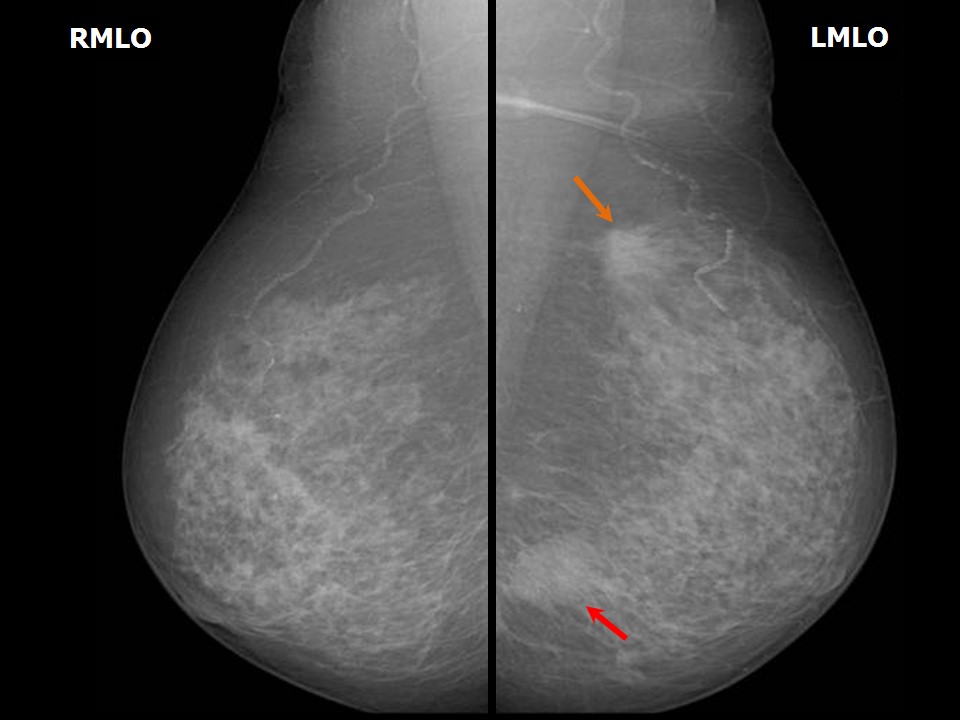

Atlas of breast cancer early detection Breast Mass Meaning How your breasts should feel. Breast cancer is a kind of cancer that begins as a growth of cells in the breast tissue. Mastitis, or an infection of the breast. Finding a lump in your breast can be scary because your initial thought may be breast cancer. A breast lump is a mass, growth, or swelling within the breast tissue.. Breast Mass Meaning.

Atlas of breast cancer early detection Breast Mass Meaning Mastitis, or an infection of the breast. While lumps in the breast don’t always mean cancer, they. After skin cancer, breast cancer is the most common. A breast lump is a mass, growth, or swelling within the breast tissue. Finding a lump in your breast can be scary because your initial thought may be breast cancer. A breast lump that's. Breast Mass Meaning.